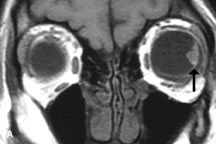

Tl relaxation time is the time required for the energized nuclei to give up the excess energy that was acquired from the RF pulse (high-energy state) and re-establish equilibrium (low-energy state) with the main magnetic field. The excess energy is released by these excited nuclei to the surrounding molecular environment, or lattice, and results in T1 relaxation, also called spin-lattice relaxation time. In different biologic tissues, hydrogen has a Tl ranging from a few hundred milliseconds to a couple of seconds. This range exists because local tissue factors affect the ability of specific protons to give up energy to the surrounding tissues. For example, hydrogen atoms attached to the carbon atoms of fat molecules relax much more rapidly than those attached to the oxygen atoms of water molecules. Viscosity, concentration, temperature, and molecular environment of the hydrogen atoms in the tissues also affect the T1 relaxation time. On a T1-weighted orbital image, fat, which has a very short T1 relaxation time, yields a high-intensity signal; the rectus muscles, which have an intermediate T1, yield an intermediate-intensity signal; and the vitreous, which has a long T1, yields a low-intensity signal (Fig. 8).5,8,16